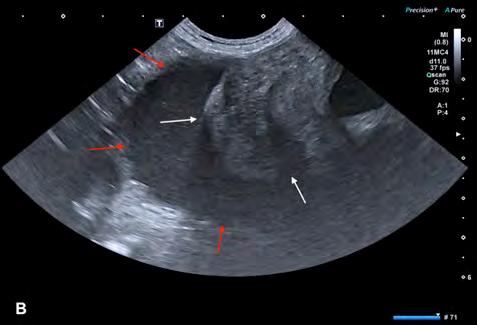

Se excluyeron del estudio los pacientes con patologías concomitantes a la ECDM, tanto cardíacas como de otros sistemas orgánicos, excepto la presencia de hipertensión pulmonar estimada mediante ecocardiografía. Se realizó la medición del volumen del atrio izquierdo con el método monoplano sumatorio de discos (MOD)9 a partir de la técnica de Simpson, que consiste en la medición del volumen del AI mediante la suma de los volúmenes de diferentes discos contiguos perpendiculares al eje mayor del AI generados por el software del ecógrafo, tras trazar el área del AI y su eje mayor de forma manual. Esta medición se realizó desde el corte paraesternal derecho longitudinal de 4 cámaras en telesístole, previo a la apertura de la válvula mitral (Fig. 1). Se siguió el borde endocárdico del atrio izquierdo, previo a la apertura de la válvula mitral en la telesístole cardíaca, sin incluir las venas pulmonares. Posteriormente, lo correlacionamos con el peso del paciente realizando la ratio: LAv/BW = volumen del atrio izquierdo (ml) / peso del paciente (kg).1,2,6

Se llevó a cabo el estudio estadístico mediante el uso de un software comercial (Statgraphics, Statgraphics Technologies, Virginia), realizando una prueba ANOVA y Kruskal-Wallis. Se valoró si existían diferencias estadísticamente significativas (p<0,001) entre las medias y medianas de los diferentes estadios de la ECDM en la ratio LAv/BW, principalmente de los pacientes en estadio B2 y C7 de la enfermedad. Posteriormente, se valoró la especificidad y sensibilidad de este método para la detección de pacientes en ICC izquierda o según las guías ACVIM en estadio C7 mediante las fórmulas “sensibilidad = (animales realmente positivos/ positivos totales) x 100” y “especificidad = (animales realmente negativos/ negativos totales) x 100”, utilizando el valor de corte ≥2,25 ml/kg.1 Esto permitió estimar si esta medida discriminaba entre pacientes con congestión venosa y sobrecarga de presión en el atrio izquierdo, es decir, pacientes que según los criterios de

Figura 1. ECDM. (A) Medida mediante MOD del volumen del AI. (B) Corte paraesternal derecho 4 cámaras, zoom AI. Ratio LA/BW = 3, 8 ml/kg.

las guías ACVIM para la ECDM se encontrarían en un estadio C y, por tanto, en ICC izquierda, de los pacientes sin enfermedad cardíaca descompensada.